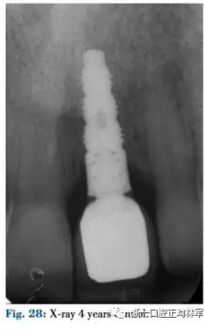

修復階段

4月后在個性化基臺上粘臨時牙促進組織成熟,8月后修整,最后用全瓷冠修復(圖26-29)。